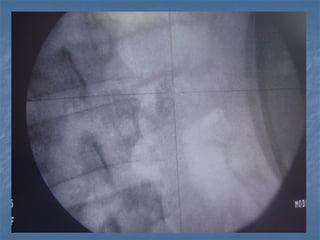

Aguja de punción y fluoroscopia

Aguja de puncióny fluoroscopia